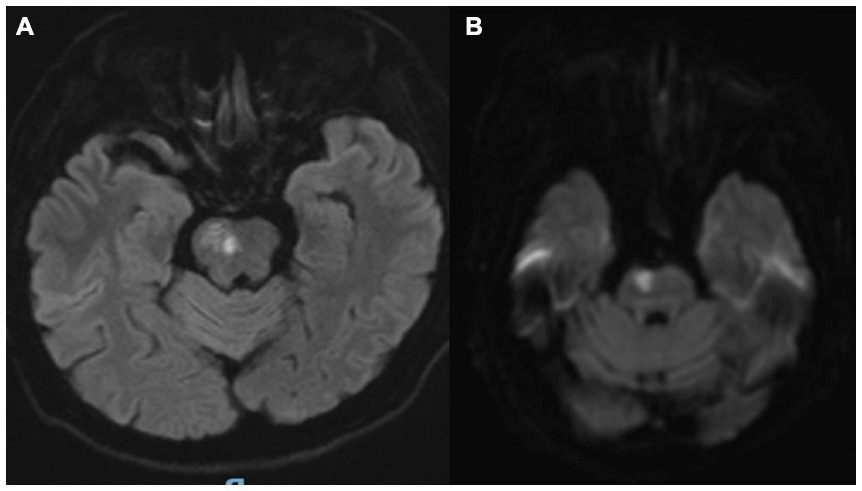

A 62-year-old woman presented to our institution with a 5-day history of dysarthria, left-sided limb numbness and weakness, and nocturnal behavioral disturbances. The patient initially reported isolated left finger numbness upon awakening, without accompanying dizziness or motor deficits. Over the subsequent 72 h, her condition progressed to include dysarthria, left hemiparesis (Medical Research Council grade 3/5), and intermittent dysphagia, accompanied by hypersomnolence and recurrent nocturnal episodes of disorganized vocalizations, agitated shouting, and complex motor behaviors during sleep. Neuroimaging (MRI) demonstrated an acute infarction involving the right pontine tegmentum and rostral midbrain (Figure 1). Her medical history was significant for longstanding hypertension (≥10 years), poorly controlled (mean BP 165/95 mmHg pre-admission), with no prior history of parasomnias or neurodegenerative symptoms. We conducted a structured interview with the patient’s spouse using the Innsbruck RBD Inventory (Stiasny-Kolster et al., 2010), which revealed that the patient had no history of dream-enactment behaviors prior to the onset and no observed nocturnal vocalizations or complex movements before disease onset.

Figure 1. (A,B) Brain MRI confirmed an acute ischemic lesion involving the right pontine tegmentum and midbrain.

Brain MRI confirmed an acute ischemic lesion involving the right pontine tegmentum and midbrain (Figures 1A,B). Transcranial Doppler and cervical duplex ultrasonography identified right vertebral artery occlusion, reduced flow velocities in the left vertebral artery (28 cm/s vs. normal >40 cm/s), and the basilar artery (35 cm/s), along with bilateral carotid intima-media thickening (1.2 mm) containing non-stenotic heterogeneous plaques.